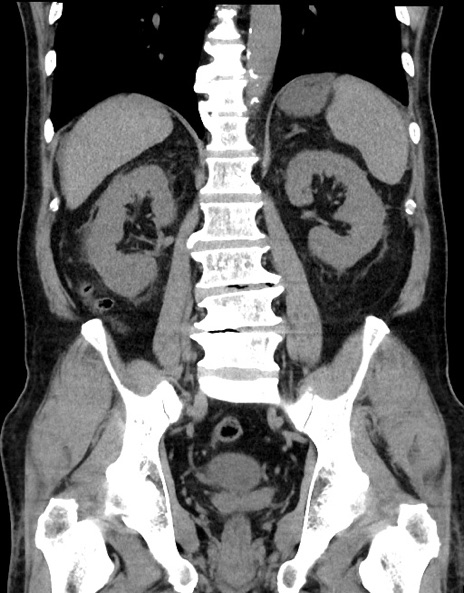

症例15(冠状断像)

【症例】70歳代男性

【主訴】腹痛

【現病歴】今朝から腹痛あり。全体的に痛い。特に左上の方。排ガスが今日はない。冷や汗が出る。

【既往歴】直腸癌術後

【身体所見】左側腹部〜上腹部に圧痛あり。腹膜刺激症状明らかなではない。軽度反跳痛。左下腹部に術後瘢痕あり。

【データ】WBC 7700、CRP 0.02